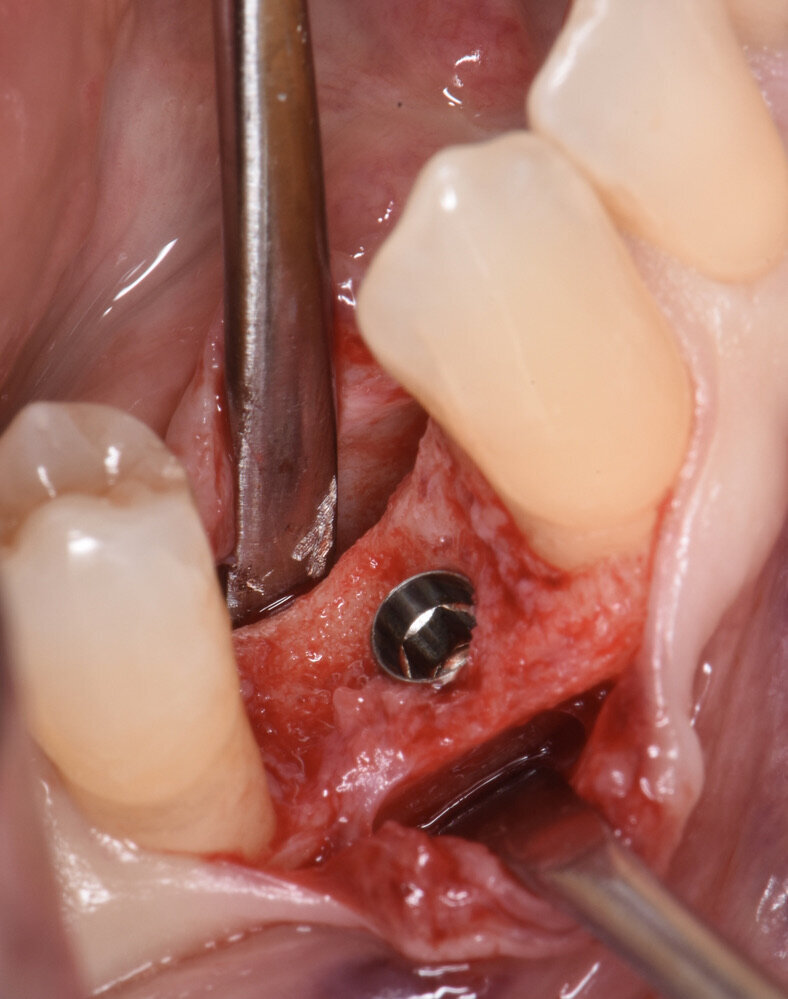

Prima dell’estrazione (S0), ad ogni paziente è stata eseguita una scansione intraorale tramite scanner iTero (Align Technology) (Fig. 2), e le scansioni sono state archiviate. A distanza di 2 mesi dall’estrazione è stato creato un lembo vestibolare a busta, a mezzo spessore, è stato inserito l’impianto nel sito (Figg. 3, 4) ed è stata posizionata la matrice in collagene suino volumetricamente stabile Geistlich Fibro-Gide (Geistlich Pharma), stabilizzandola al periostio con due punti di sutura riassorbibili interni (Fig. 5)7. Il lembo è stato quindi suturato con suture non riassorbibili e punti sospesi in modo da garantire la chiusura primaria e mantenere la matrice sommersa ma non compressa (Fig. 6).